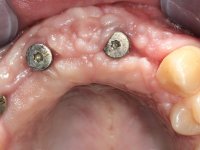

Paciente do sexo masculino, com 22 anos de idade e não fumador. Apresentou-se na consulta 6 meses após um acidente de viação em que perdeu os dentes 21, 22, 23 e 24. Os dentes 12 e 11 apresentavam mobilidade grau 3 apresentando-se também com extracção indicada. A arquitectura gengival da zona desdentada apresentava-se retraída e planificada.

O paciente foi observado conjuntamente e a dúvida que surgiu de imediato foi se seria possível com a regeneração óssea a efectuar poder ser reabilitada naturalmente a zona das papilas interdentárias. Nesse sentido foi feito um enceramento de diagnóstico que contemplaria as duas hipóteses, utilizando ou não a cerâmica gengival. A confecção desse enceramento foi fundamental para expor ao paciente a dificuldade da reabilitação. O wax-up deu origem a um mock-up que foi aprovado pelo paciente e que simultaneamente serviu de guia imagiológica. O caso foi planificado cirurgicamente e realizada uma guia cirúrgica com que foram colocados os implantes. Após 10 semanas foi feita a 1ª impressão para confecção da ponte provisória. Foram criados os primeiros perfis de emergência na gengiva artificial e foi digitalizado o modelo. Por processo de CAD-CAM foi confeccionada uma ponte provisória aparafusada baseada no enceramento de diagnóstico. A ponte trabalhou durante 8 semanas os tecidos moles que foram fielmente copiados numa impressão com técnica de moldeira aberta. Os transferes foram individualizados com resina composta para copiarem fielmente os perfis de emergência criados pela ponte provisória. Confeccionado o modelo de trabalho definitivo, foi realizada uma infra-estrutura em zircónio seguindo a orientação do enceramento de diagnóstico. O assentamento da infra-estrutura foi testado em boca e simultaneamente foi novamente impressionados os tecidos moles com um silicone fluido. Nessa consulta foi feito o levantamento da cor. Os dentes 13 e 23 apresentavam uma saturação anormalmente forte que resolvemos não valorizar, optando por privilegiar a relação com o sector antero-inferior. Foi realizada uma nova gengiva artificial com a impressão que acompanhou a impressão de arrasto com a infra-estrutura. Após a colocação da cerâmica na infra-estrutura foram coladas as meso-estruturas. O trabalho final foi aparafusado lentamente permitindo a adaptação dos tecidos moles.